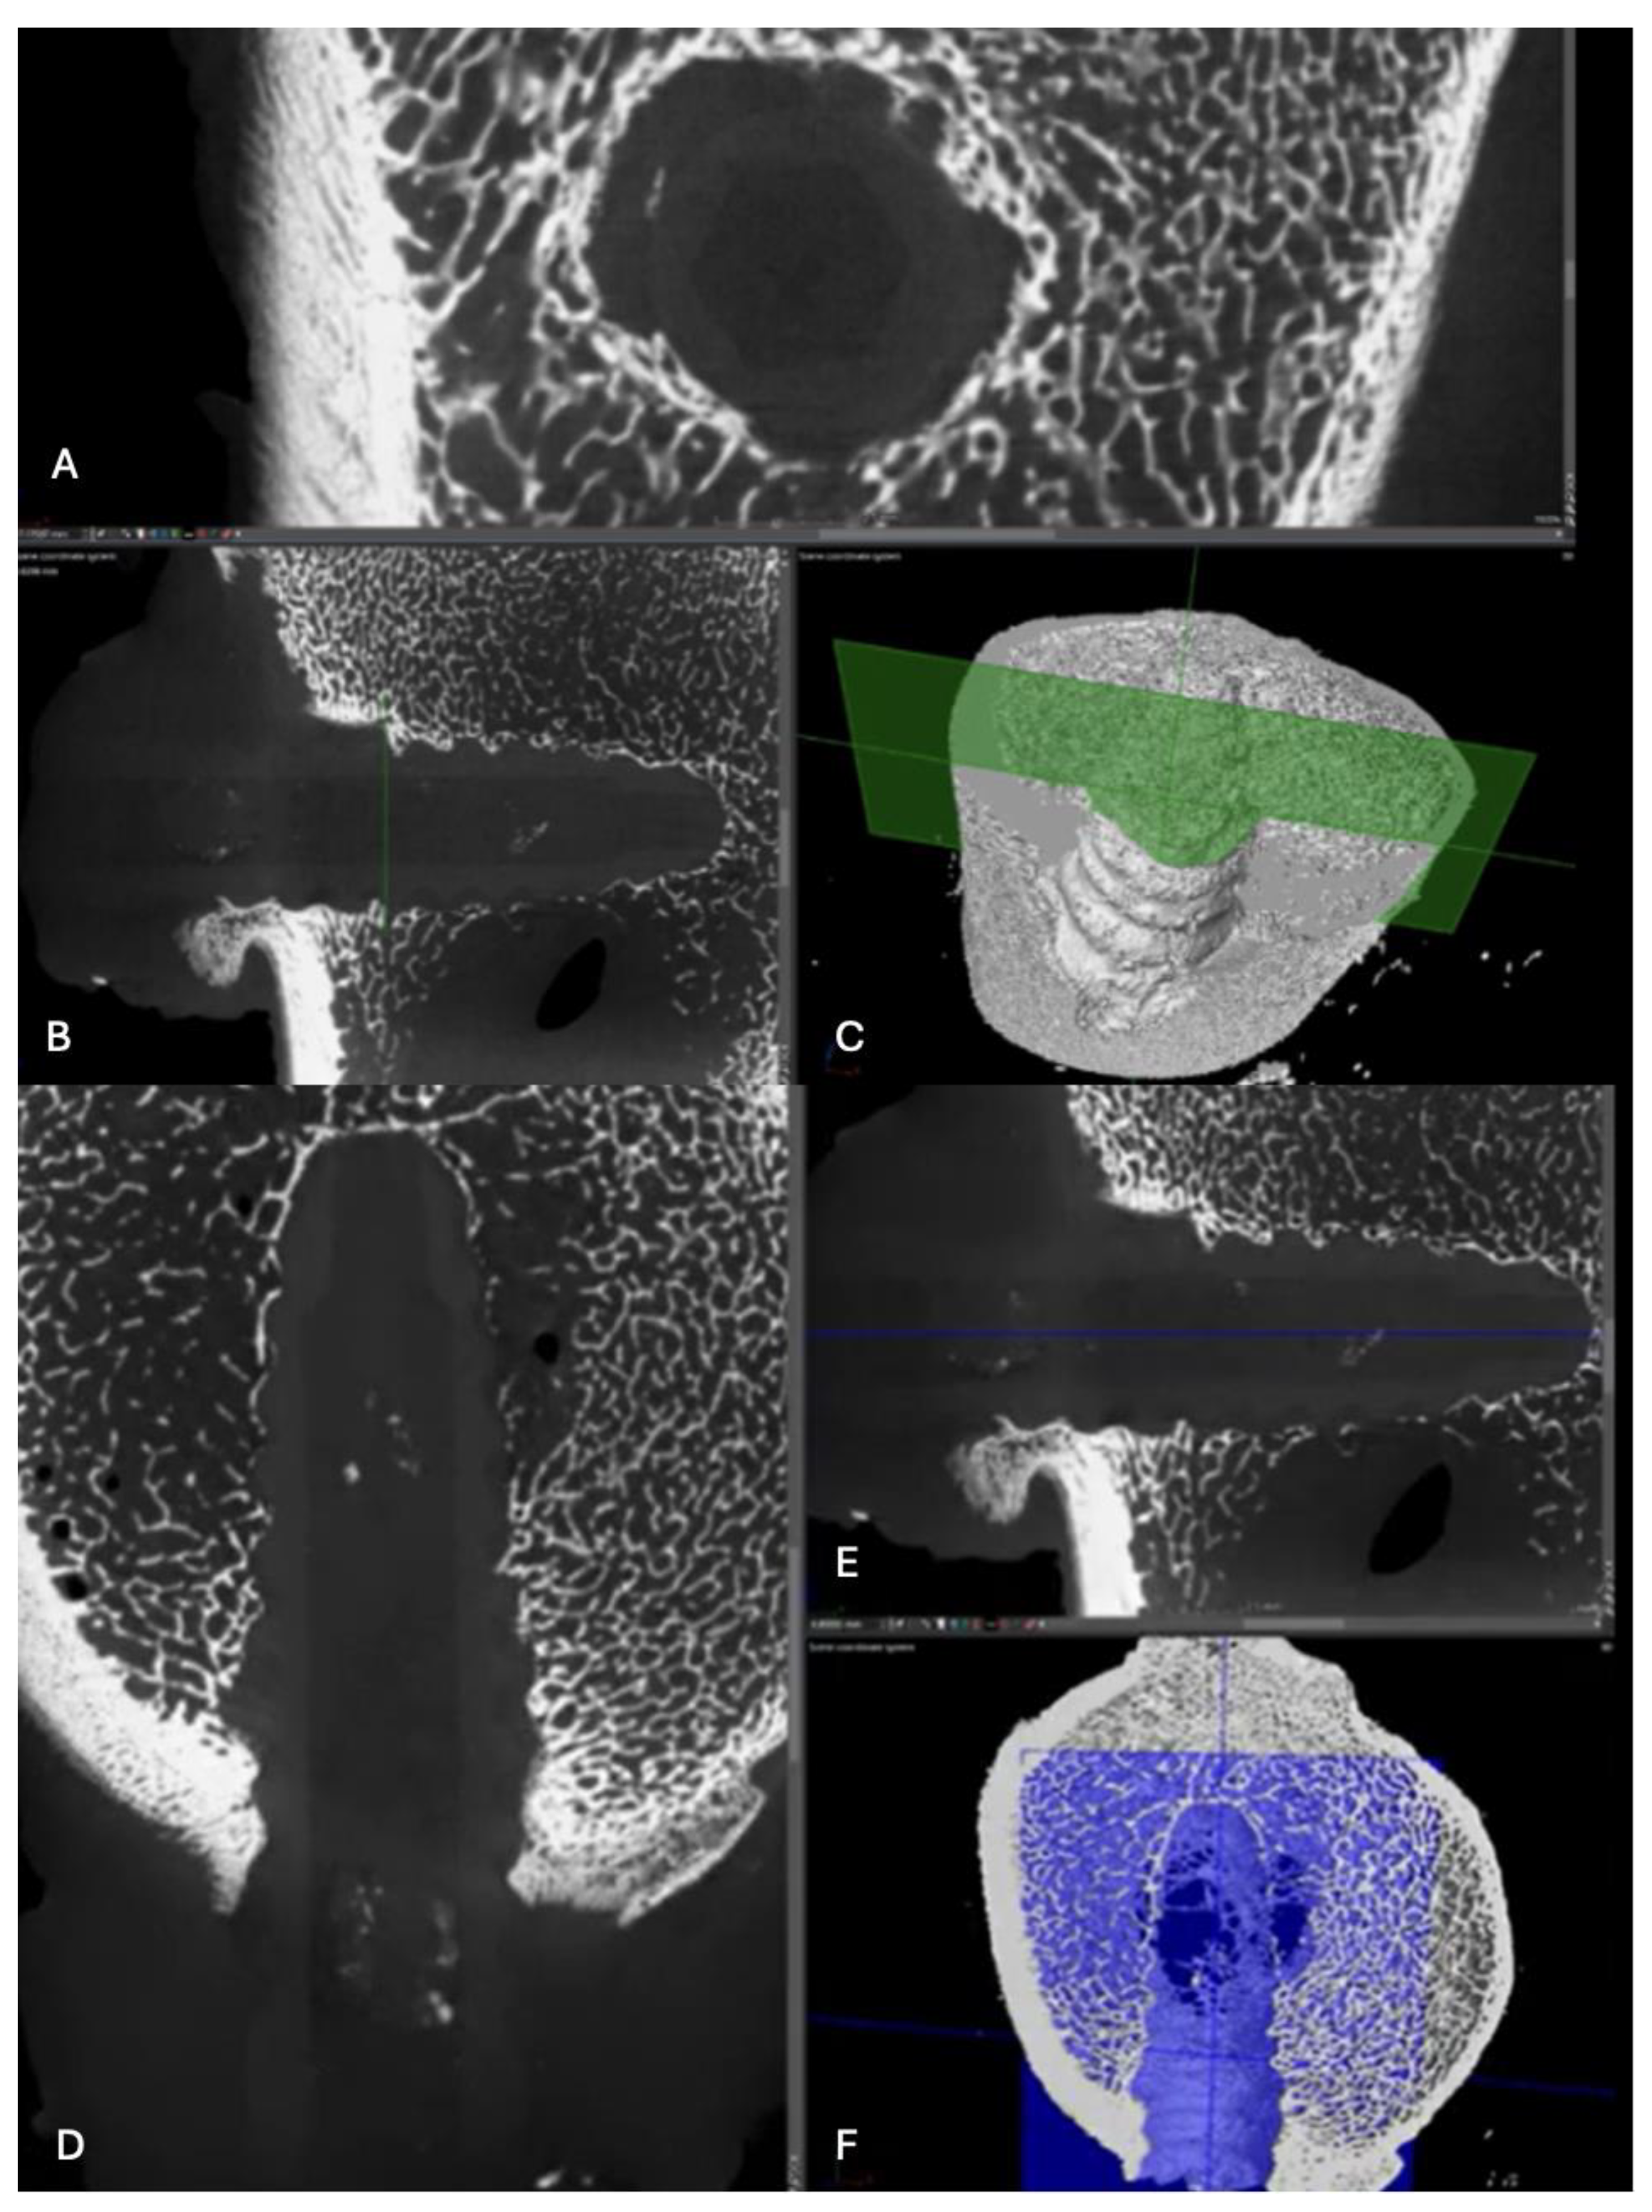

Figure 14. Computed tomography study (A) axial slice, (B,D,E,F) sagittal reconstruction, and (C) 3D visualisation of the left femur sample, one-month post-surgery, with PLDLLA material.

PLDLLA: In a 3D reconstruction view, the screw appears circumferentially, with a slight increase in bone density around it, suggesting initial bone growth that has not yet fully reached the implant. In the lateral view, slight bone growth is evident, with more development in the proximal third of the screw, indicating more pronounced consolidation in that area. Additionally, small hyperdensities within the screw suggest the presence of bone growth inside it. These findings reflect early progress in the osteogenic response and screw integration, although the consolidation process is still in its initial stages. (Figure 14)

Figure 20. Computed tomography study of the left femur sample, three-month post-surgery, with PLDLLA material. (A, F)Axial and (B,C,D,E) sagittal reconstruction.

PLDLLA: In a 3D reconstruction, the sagittal view reveals a circumferentially shaped screw. A hyperdense area is observed in the mid-third region of the screw, indicating ongoing bone growth. The lateral view confirms proper positioning of the screw within the femoral tunnel, occupying approximately 60% of the insertion tunnel. (Figure 20)